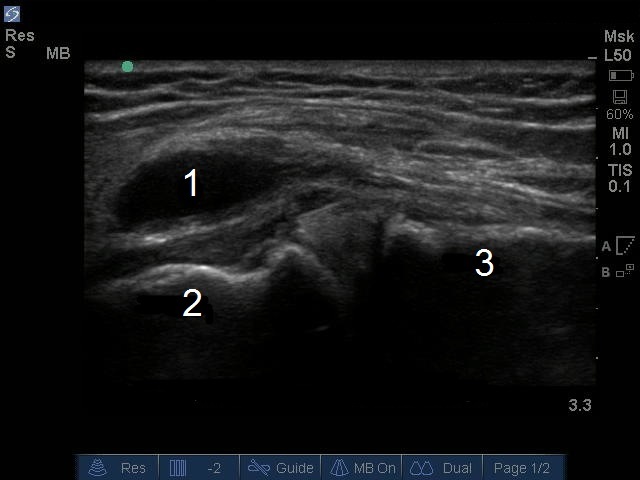

Image : Genou : Kyste du ménisque médial avec gonflement proximal

1. Kyste du ménisque médial

2. Fémur

3. Tibia